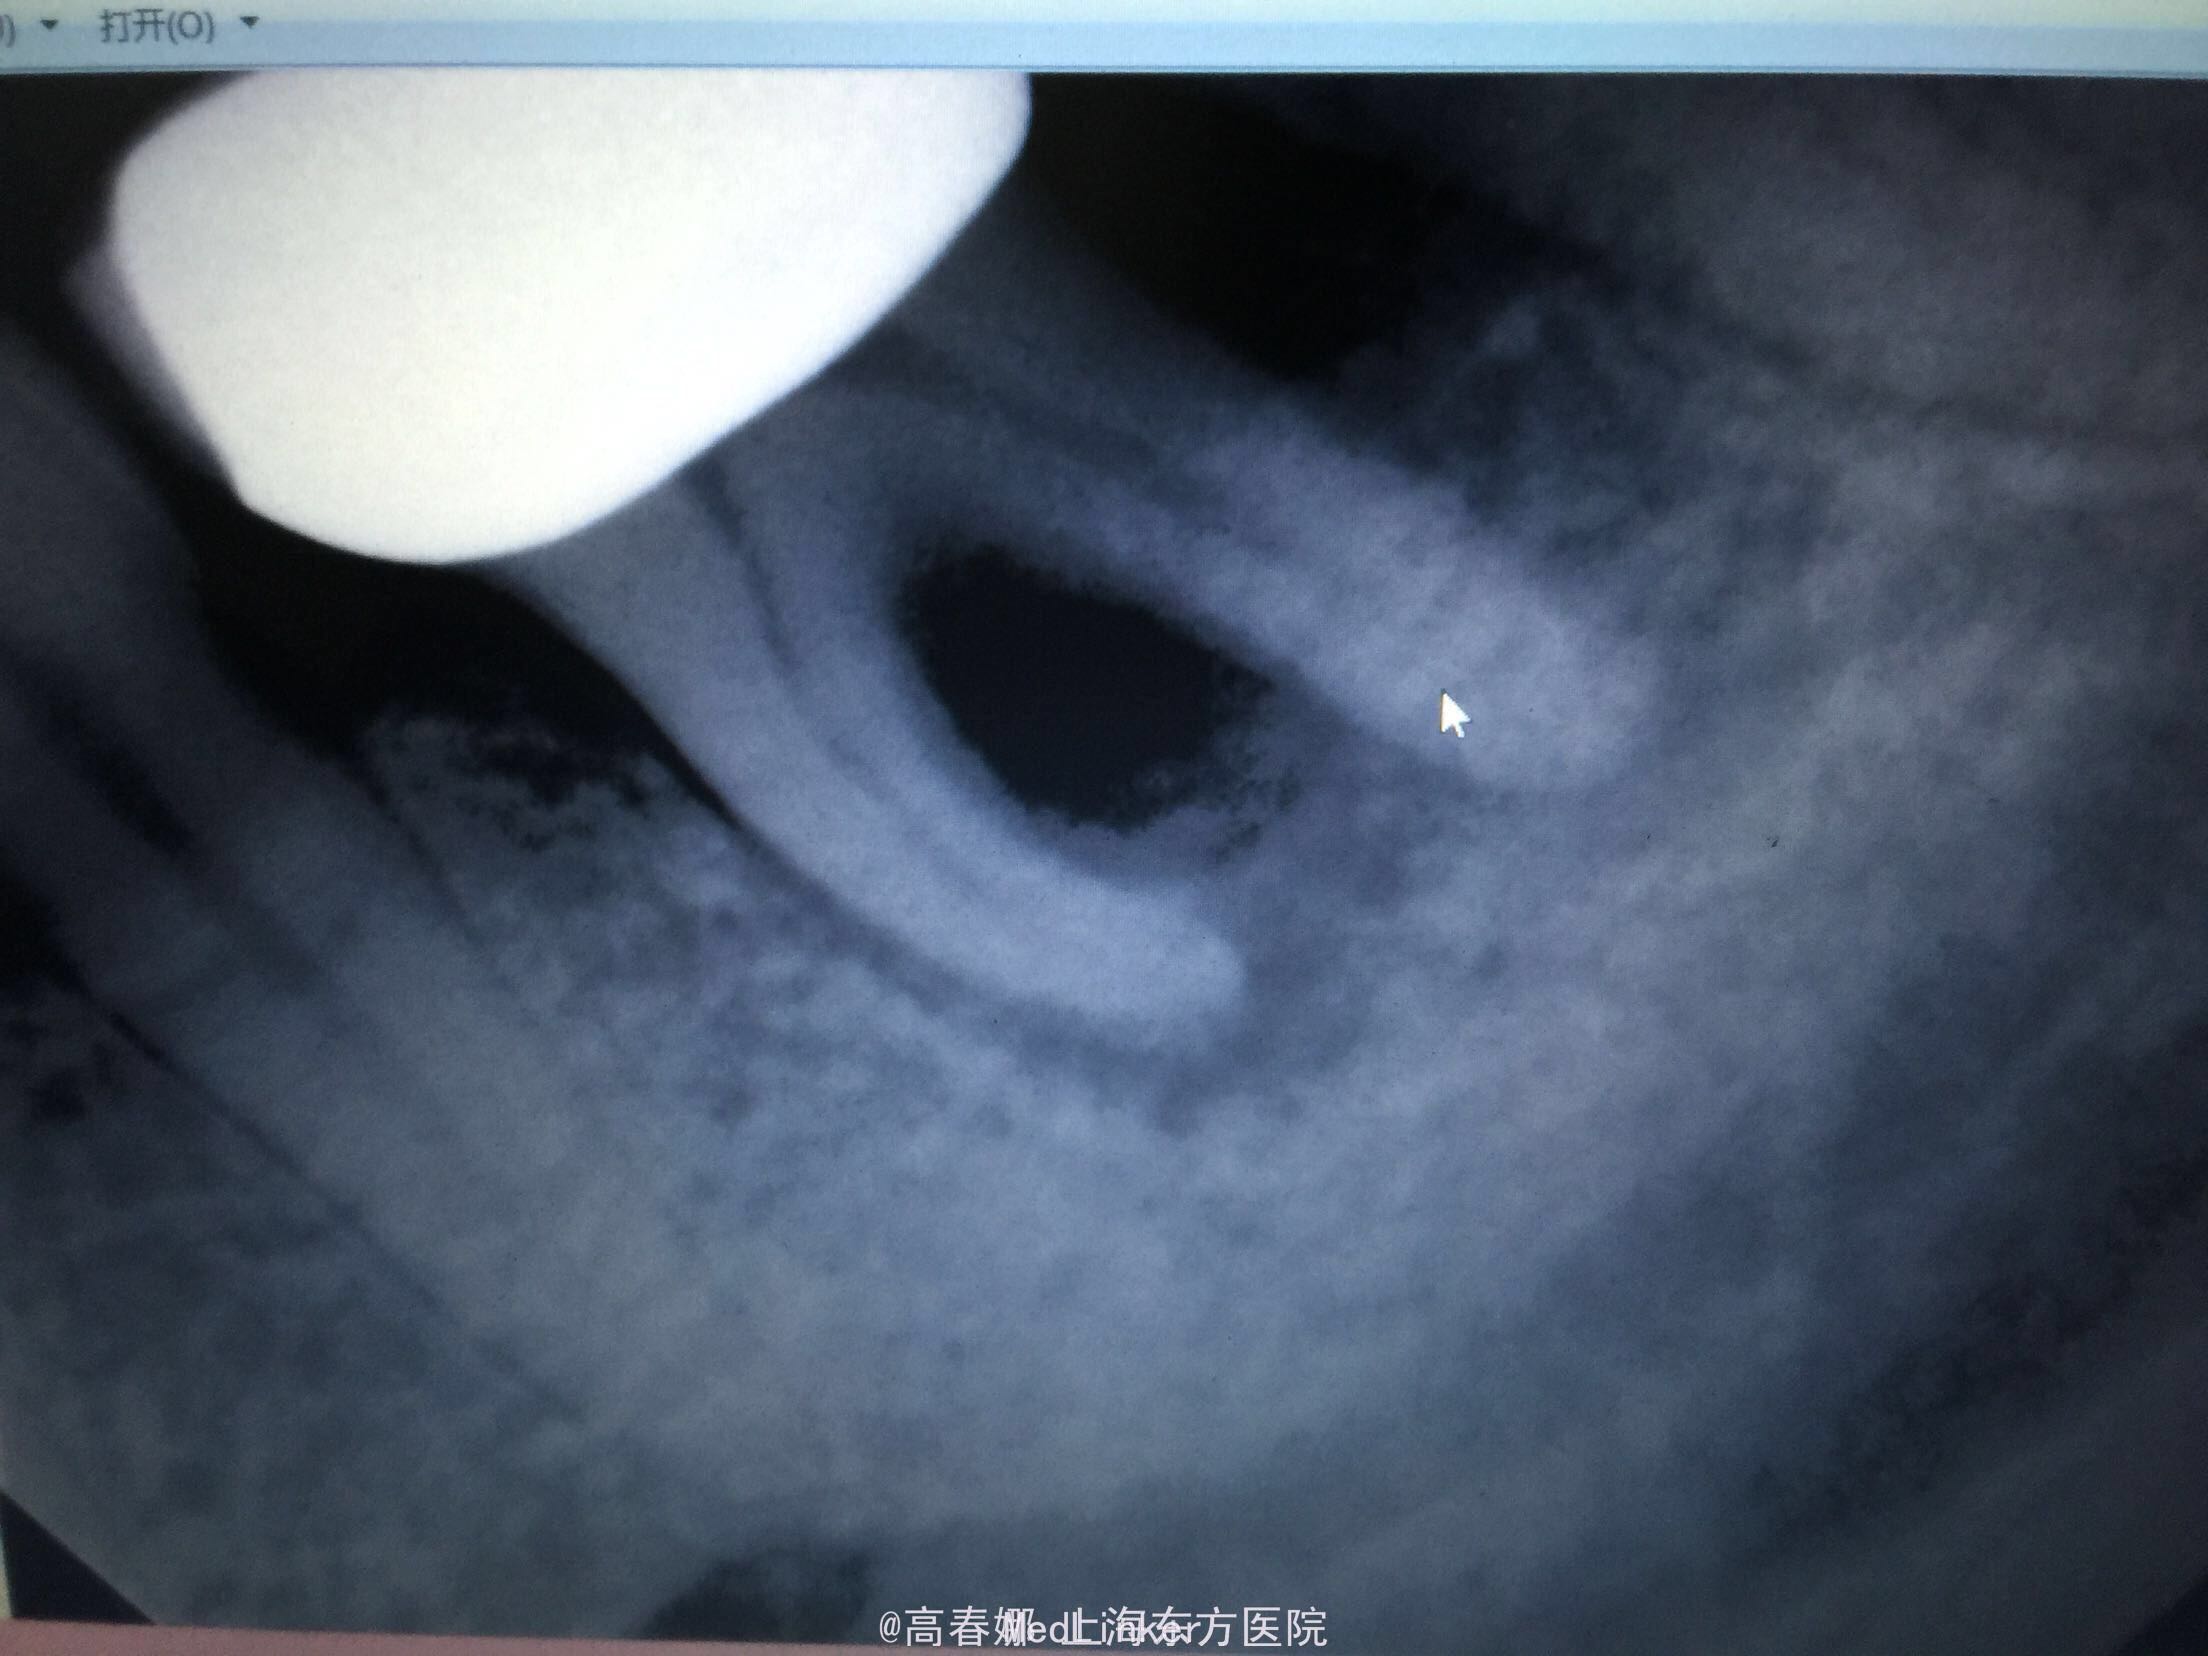

检查:36冠修复,叩诊(+-),松动II度,颊侧牙龈瘘管,牙周袋约3mm,根分叉未探及,冷(-)。 X线示:36根尖区及根分叉区大面积阴影。

随访:三个月复查,牙龈未见明显红肿及瘘管,36扣痛无,松动物。X线示:36根尖及根分叉骨密度增高。